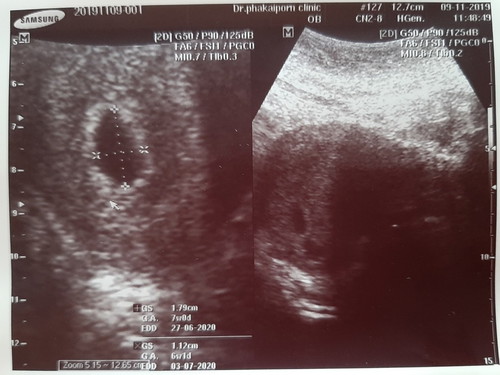

เมนต์ไม่มาตั้งแต่วันที่ 22 ตุลาคม มาถึงวันนี้อายุครรภ์น่าจะได้ สัปดาห์ที่ 6 แต่พอไปอัลตร้าซาวดู หมอบอกว่ามีถุงน้ำโตขึ้น แต่ยังไม่เห็นตัวเด็ก

ซาวด์ทางหน้าท้องหรือช่องคลอดคะแม่ ถ้าทางหน้าท้อง ถ้าตัวอ่อนยังเล็กมากๆ หรือเป็นคนหน้าท้องหนา อาจจะยังไม่เห็นค่ะแม่ ทางช่องคลอดจะพอมีลุ้นมากกว่าค่ะ ทั้งนี้เป็นไปได้ว่า อายุครรภ์อาจจะน้อยกว่าที่นับ เพราะไข่อาจจะตกช้ากว่ากำหนด ตัวอ่อนยังเล็กมากอยู่ จึงยังไม่พบ ก็เป็นได้ค่ะแม่ ทานโฟลิคทุกวัน พักผ่อนเยอะๆ นะคะ ซาวด์ครั้งหน้าอาจจะได้เจอกันแล้วจ้า

อ่านเพิ่มเติมบ้านนี้เจอน้องตอน9wค่ะ 5wซาวด์เจอแต่ถุง